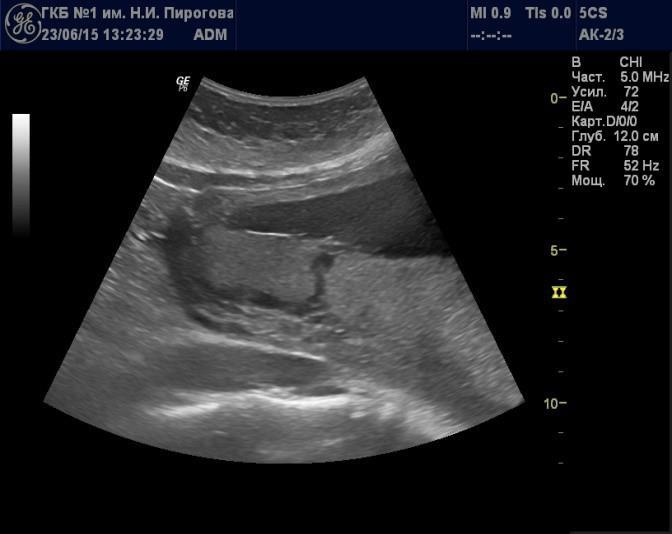

Выявляемые при серошкальном исследовании плаценты ан- или гипоэхогенные зоны чаще всего являются эхографическими срезами участков расширения ее МВП (Рис. 7) и значительно реже сосудов плода (Рис. 8). Расширение МВП может быть связано как с поступлением материнской артериальной крови, и отражать одно из состояний артериального капиллярного русла маточно-плацентарного кровотока (Рис. 9), так и с оттоком в материнское русло венозной крови (Рис. 10). При этом направление тока крови может быть установлено при цветовом допплеровском картировании (ЦДК). Следует иметь в виду, что венозное звено маточно-плацентарного кровообращения состоит из двух функциональных частей: венозных коллекторов плацентарного ложа возле разделительных септ и краевых синусов [10], которые также могут быть расширены (Рис. 11).

Рис. 10. Беременность 20 нед. Расширение межворсинкового пространства, связанное с венозным оттоком, в серошкальном режиме (а) и режиме цветового допплеровского картирования (б).